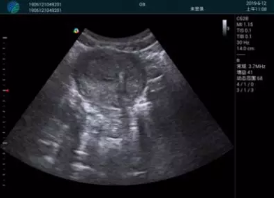

清晰顯示孕囊,通過軟件包計算孕齡7w+6d

M20實時引導,術(shù)中清晰顯示孕囊被破壞和抽吸針的過程,清晰顯示吸引針

抽吸結(jié)束后縱切子宮,孕囊已被完全抽吸,未見明顯殘留

橫切子宮,發(fā)現(xiàn)右側(cè)宮腔靠近宮角處有少許脫模樣殘留

M20引導下,抽吸針找到右側(cè)宮角處再次清掃

二次抽吸后再次進行超聲檢查,宮腔未見殘留,宮腔線清晰顯示